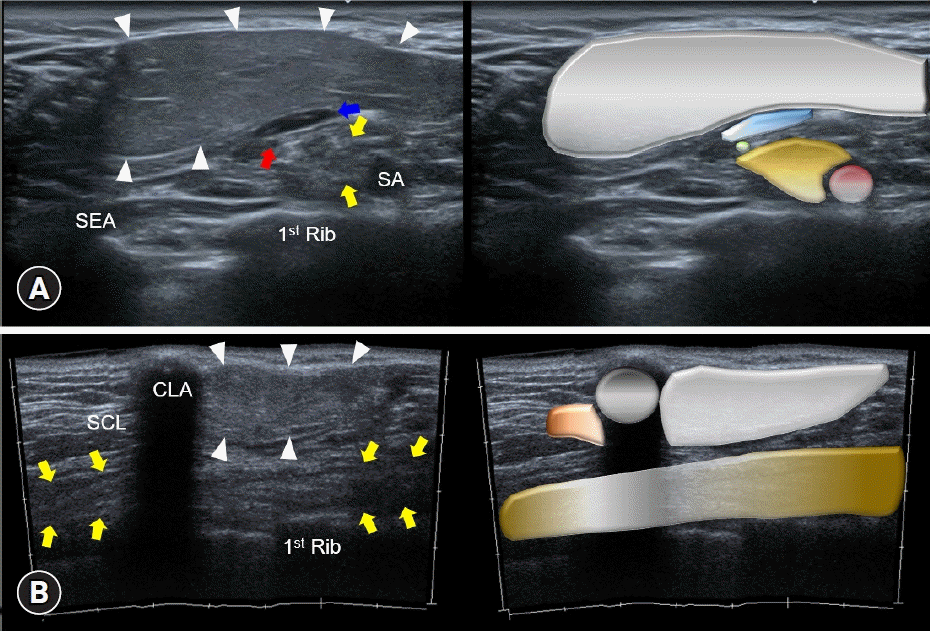

During the examination, a bulging area in the supraclavicular region was observed without apparent skin color changes. Palpation revealed an elastic superficial mass with no sensory or motor deficits in the left upper extremity. Following ultrasound examination of her left suprascapular region, a well-demarcated hypoechoic mass measuring 7.1×3.5×3.6 cm was identified in the subcutaneous layer, exhibiting several hyperechoic strata. The mass was located over the brachial plexus. While talking, the omohyoid muscle glided under the mass over the suprascapular nerve (Fig. 1A). Rotation of the ultrasound transducer along the long axis of the brachial plexus revealed the anterior edge of the mass, which approximated the clavicle but did not extend to the infraclavicular region (Fig. 1B). Given the impression of a supraclavicular lipoma (with potential entrapment of the brachial plexus), the patient was referred for surgery.

Fig. 1.

Ultrasound imaging and schematic representation of a supraclavicular lipoma are depicted in both the (A) short axis and (B) long axis views of the brachial plexus. The supraclavicular lipoma (arrowheads) is a well-demarcated hypoechoic mass. The brachial plexus (yellow arrows), omohyoid muscle (blue arrow), and suprascapular nerve (red arrow) are present. SEA, serratus anterior muscle; SA, subclavian artery; SCL, subclavius muscle; CLA, clavicle.